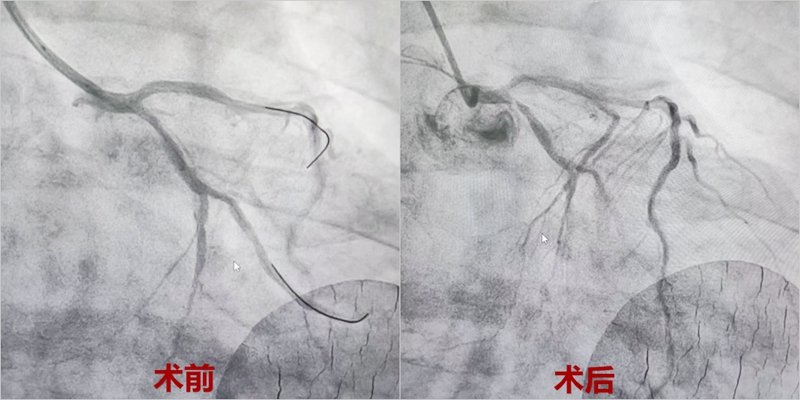

董伯被紧急转往玉环市人民医院,医生火速将他推进DSA导管室进行PCI(经皮冠状动脉介入治疗)手术。术中造影显示,董伯的心脏三条主要血管均存在病变,其中前降支中段已完全急性闭塞,且堵塞处的血管壁钙化十分严重,开通难度极大。

心内科副主任赖仙辉带领团队,凭借丰富的经验和精准的操作,一点点打通闭塞的血管,成功为董伯植入支架,这才从“死神”手里抢回了他的生命。